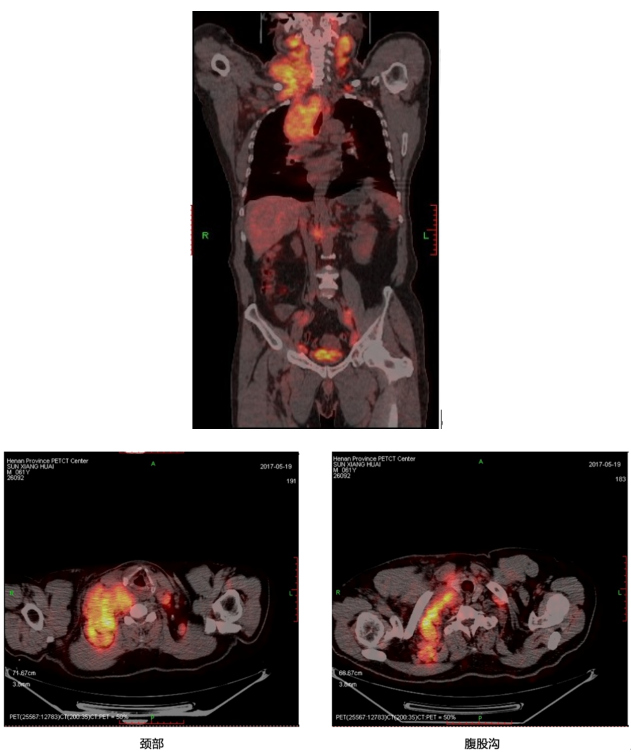

影像学检查 2017年5月18日PET-CT检查所见,鼻咽顶后壁稍增厚,放射性摄取增高,SUVmax 5.0。双侧耳前、双侧腮腺内、C2层面颈前、左侧咽旁间隙、颈部双侧Ⅰ~Ⅴ区及双侧锁骨上区见多发软组织结节影、肿块影,部分融合,较大者位于右侧锁骨上。项部皮下见多发软组织结节影,短径均小于10 mm,放射性摄取未见异常。

双侧内乳淋巴引流区、纵隔、双肺门、双侧前胸壁肌间隙、双侧腋窝见多发软组织结节影、肿块影,部分融合,邻近气管受压变形。右侧胸膜多处不规则增厚。双侧胸腔内见液性密度影,右侧为著,放射性摄取未见异常。腹腔肝胃间、肝门区、肠系膜走行区、腹膜后双侧髂血管走行区及双侧腹股沟区见多发软组织结节影。

图 患者各部位PET-CT检查图示